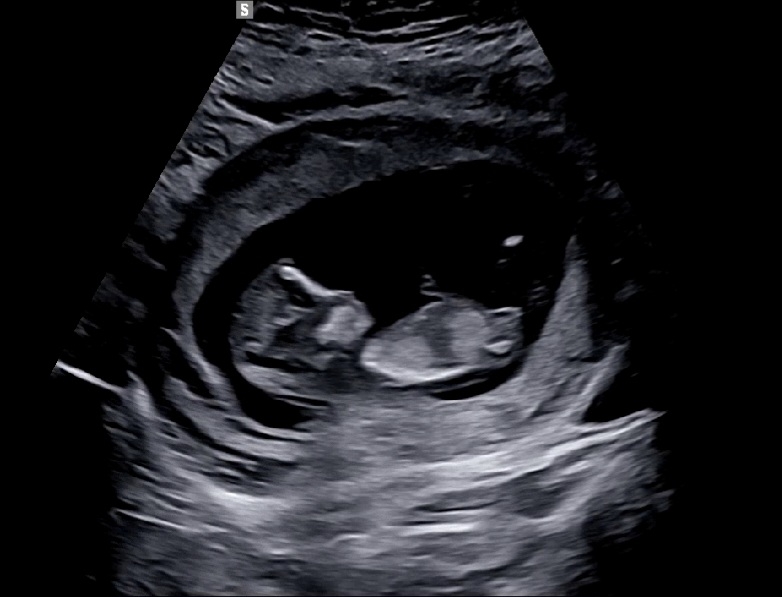

12주4일차 각도법 딸?!아들?!

아들이던 딸이던 건강하게만 태어나길 바라지만.. 궁금한건 어쩔수없네요!!! 12주차 각도 한번 봐주세용🥹

각도는 공주같아욤